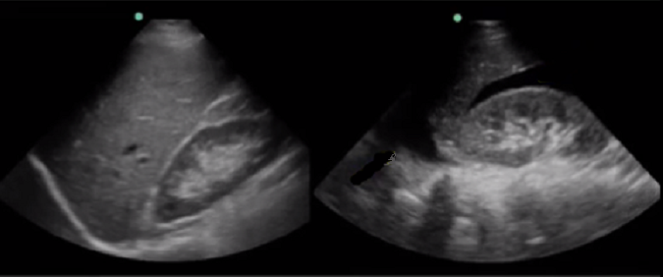

RUSH Pleural/Abdominal Fluid Yes/No Comparison Image